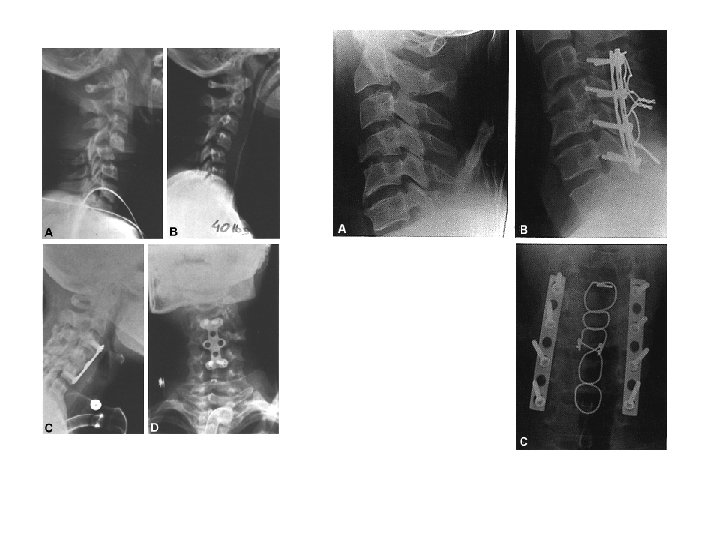

Terapi Prinsip • Konservative – bed rest 6 mg – 6 mg brace – 6 mg rehabiltation • Operatif – Screw and Plate dll • Reposisi • Immobilisasi – Eksternal – Internal